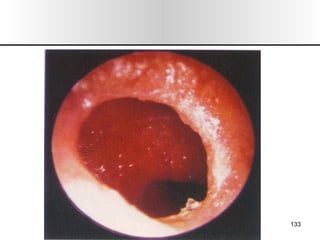

Nariz y senos paranasales

• 1.